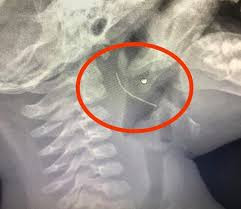

| Sợi thép đâm vào thành cổ họng cháu H. - Ảnh: Bệnh viện cung cấp |

| Sợi thép dài được các bác sĩ gắp ra từ cổ họng cháu bé. Ảnh: BV cung cấp |